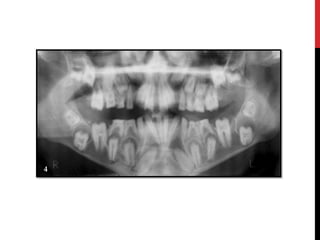

Amelogenesis imperfecta with taurodontism

(hypomaturation/hypoplastic AI)

 Combination of enamel hypoplasia with hypomaturation.

 Deciduous & permanent dentition involved.

 2 patterns.

Amelogenesis imperfecta withtaurodontism (hypomaturation/hypoplastic AI)  Combination of enamel hypoplasia with hypomaturation.  Deciduous & permanent dentition involved.  2 patterns.

• #31 Autosomal dominant smooth pattern: The enamel of all teeth exhibits a smooth surface and is thin hard and glossy. The absence of appropriate enamel thickness results in teeth that are shaped like crown preparations and demonstrate open contact points. The color of teeth varies from opaque white to translucent brown. Radiographically the teeth exhibit a thin peripheral outline of radiopaque enamel.

• #32 X-linked smooth pattern Exhibits diffuse thin, smooth, and shiny enamel in both dentitions. The teeth often have the shape of crown preparations,and the contacts points open. The color varies from brown to yellow-brown. Radiographs show a peripheral outline of radioopaque enamel.unerupted teeth undergo resorption. An open bite is seen in almost all males and in a minority of females. X-linked rough pattern The enamel is thin, hard and rough surfaced.As in smooth forms, the teeth taper towards the incisial occlusal surface and demonstrate open contact points. The color varies from white to yellow white. The enamel is denser than that seen in smooth patterns and the teeth are less vulnerable to attrition. Radiographs exhibit a thin peripheral outline of radio dense enamel.